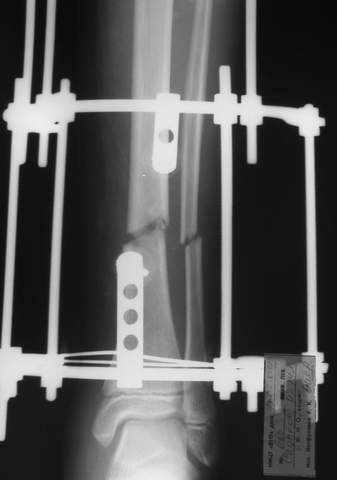

В аттачте № 3 - один из примеров полукольцевого аппарат...

Это уже я баловался.

Итог? Работы больше (по времени и

интраоп "подгонке"), срастается также, а особого преимущества по сравнению с

"чиста" кольцевым (вес, удобство ношения и пр.) - я, по крайней мере,

не нашел.

Теперь не балуюсь.

Может быть зря?